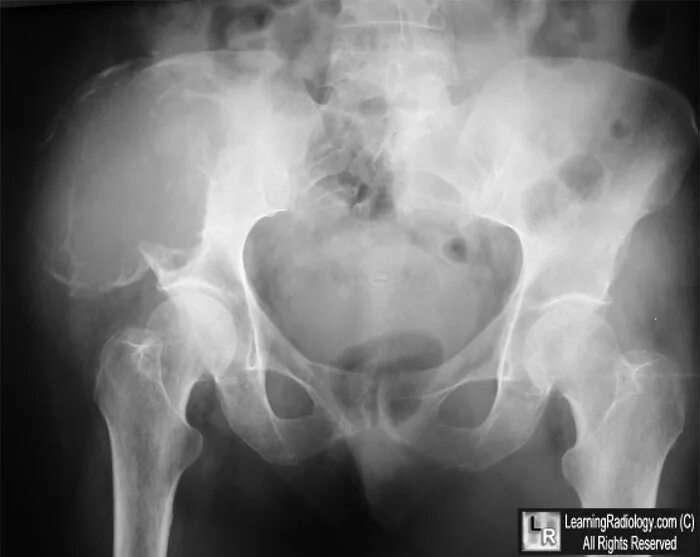

Метастазы в тазу